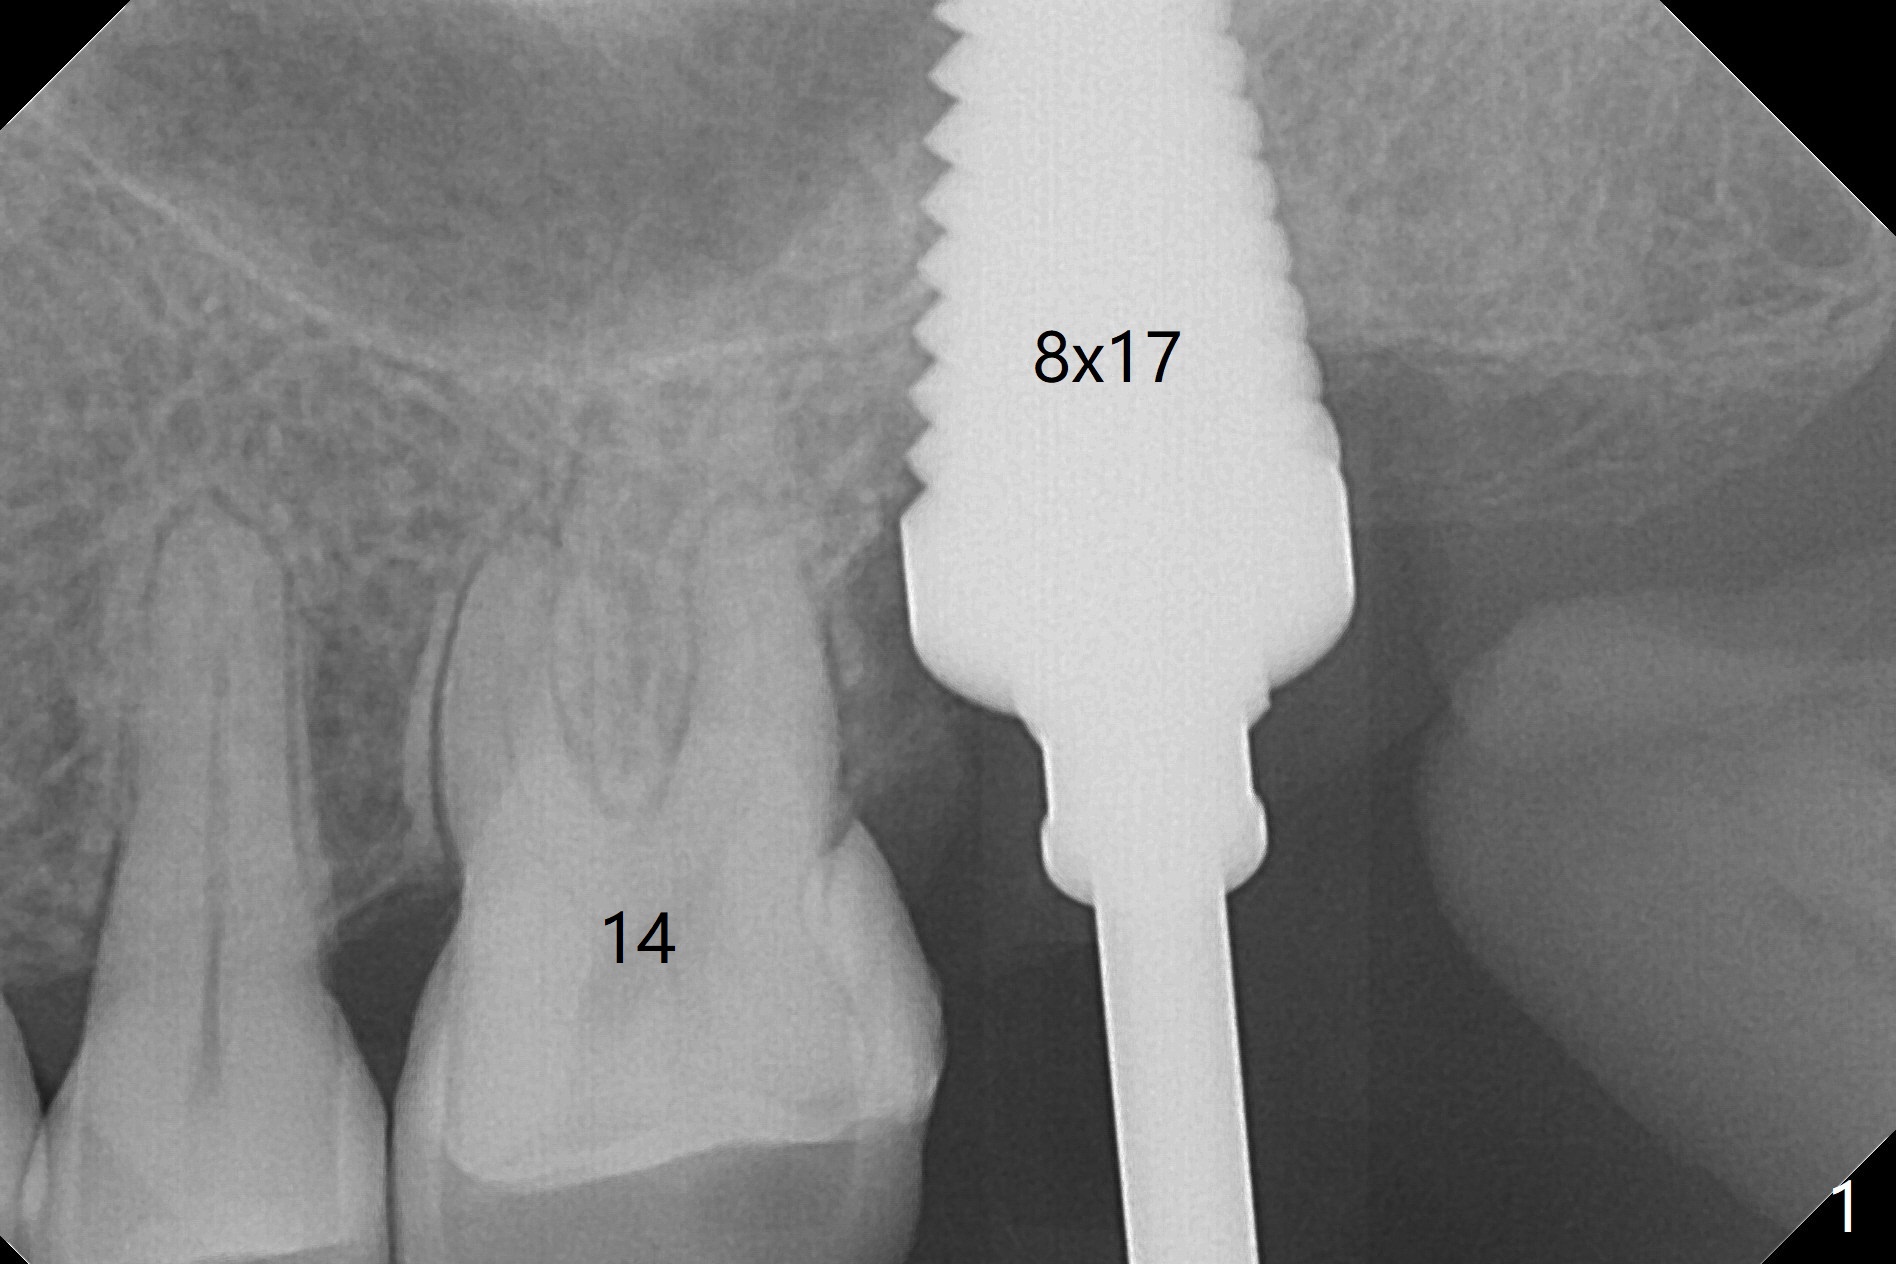

A 56-year-old woman has sign of periimplantitis 2 years 9 months post cementation. After incision, the 5.5x13 mm bone-level implant is ~ 3 mm inferior to the buccal crest. The implant is removed with 7/6 mm trephine bur, elevator and implant driver. The sinus membrane perforates. A 8x17 mm tap achieves stability (Fig.1), but the peripheral bone seems to be thin. Although a 7x14 mm tissue-level implant has stability, it is placed too deep (Fig.2). Following insertion of a piece of Osteogen plug for sinus membrane repair, a 8x14 mm implant is placed with >40 Ncm with allograft placed around the unpolished portion of the implant (Fig.3,4). A 6x3 mm abutment is placed to hold periodontal dressing in place. Because of the abutment with a slot (Fig.5 A), the periodontal dressing remains in place 4 days postop before the patient travels back home for 4 hours. In fact there is no postop sinus infection; the implant threads seems not be exposed 3 months postop (Fig.6). Because of the large implant, it is loaded early (Fig.7, 8 (Temp Bond)). Upper Molar Immediate Implant, Trajectory II 劈开术 Xin Wei, DDS, PhD, MS 1st edition 08/09/2019, last revision 04/11/2021